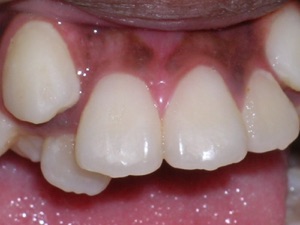

Here’s a young lady who presented with severe crowding. Often we think of crooked teeth as being limited to front teeth. Here one can see that back teeth can also get crowded. Braces were placed and select teeth were removed. Watch.